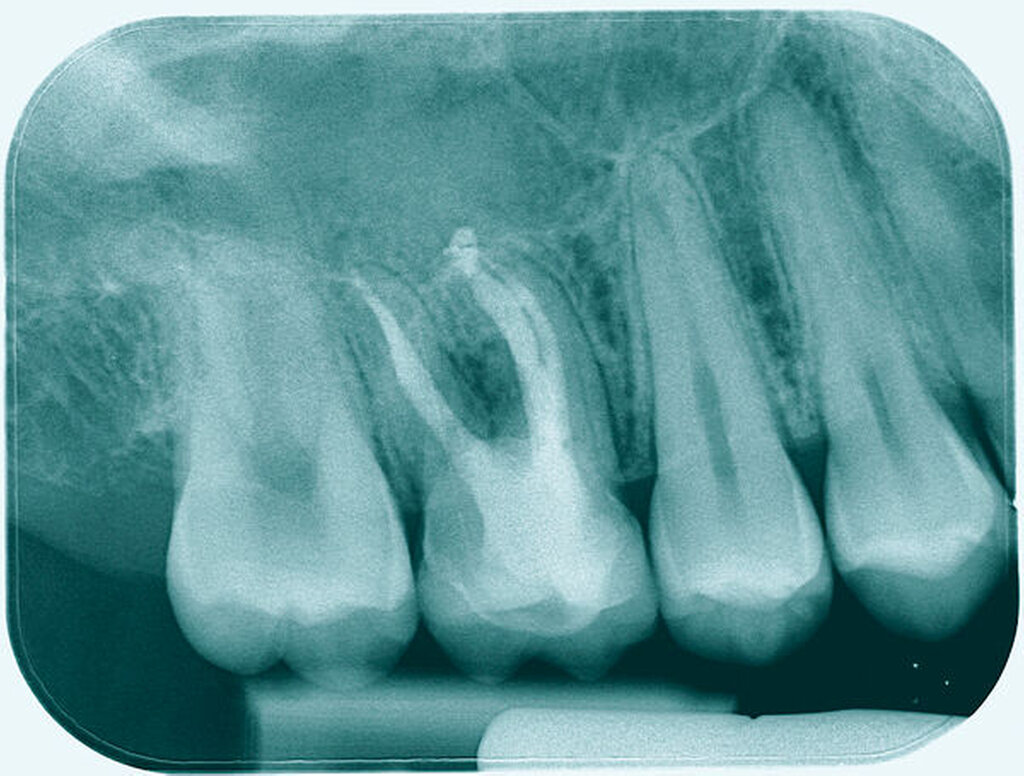

Um sicherzustellen, dass der Zahn für das gewählte Vorgehen geeignet ist, erfolgt zunächst die Auswertung der vorliegenden Röntgenbilder, eine ausführliche parodontale Sondierung des Zahnes mit Parodontalsonde und Nabers-Sonde, um Attachment und Furkationsbefall sowie möglicherweise tastbare anatomische Besonderheiten zu beurteilen. Das Röntgenbild besitzt zwar eine nur eingeschränkte Aussagekraft bezüglich des interradikulären Knochenangebots [Eickholz, 2010; Topoll et al., 1988], das durch das DVT besser beurteilbar zu sein scheint [Walter et al., 2010], jedoch waren die in diesem Beitrag gezeigten Fälle durch die Kombination aus klinischer und röntgenologischer Diagnostik ausreichend beurteilbar, um eine Therapieplanung ohne DVT durchzuführen.

Eine 46-jährige Patientin klagte 2014 über wiederkehrende Beschwerden an Zahn 16, die sich auch nach einer endodontischen Behandlung nicht besserten. Wiederholt waren submuköse Abszesse aufgetreten. Lokalisiert war die Sondierungstiefe stark erhöht, was auf eine Längsfraktur der mesiobukkalen Wurzel hindeutete. Die Patientin wurde über die Möglichkeiten der Amputation der mesiobukkalen Wurzel sowie alternativ der Extraktion des Zahnes aufgeklärt und entschied sich für den Versuch des Zahnerhalts mittels Teilamputation der mesiobukkalen Wurzel.

Eine 53-jährige Patientin stellte sich 2015 mit plötzlich aufgetretenen, starken Beschwerden an Zahn 16 und der Bitte um Abklärung vor. Es erfolgte die klinische und röntgenologische Befundung des Zahnes, der neben einer apikalen Parodontitis auch eine große, fast bis in die Furkation reichende Kronenrandkaries an der mesiobukkalen Wurzel aufwies. Um diesen vorhersagbar versorgen zu können, wurde der Patientin die endodontische Behandlung mit Amputation der mesiobukkalen Wurzel und anschließender Versorgung mittels Vollkrone als Alternative zur Extraktion aufgezeigt. Sie entschied sich für den Zahnerhalt.